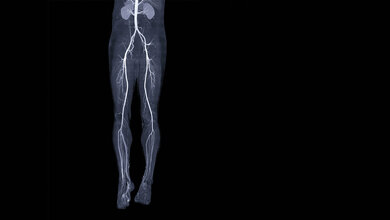

Für Prof. Verhoeven liegt der Bedarf auf der Hand: „Wir führen in den Hybrid-OPs jedes Jahr mehrere hundert Eingriffe durch. Insbesondere bei Patientinnen und Patienten mit Erkrankungen an den Arterien, etwa bei Aneurysmen, also großen Ausbuchtungen an den Hauptschlagadern, sind die Operationen höchst komplex. Bei den Operationen unterstützt uns der ARTIS pheno wie ein Navigationsgerät dabei, die nötigen Prothesen an den betroffenen Stellen punktgenau einzusetzen.“ Dank der engen Zusammenarbeit mit den Kolleginnen und Kollegen aus der interventionellen Radiologie, aber auch der Kardiologie und der Herzchirurgie rechne sich die Anschaffung von gleich zwei „ARTIS pheno“-Geräten, so die Klinik. „Ob Aneurysma, Gefäßverengung oder Aortenklappe: Im HGZ arbeiten wir interdisziplinär“, so Prof. Verhoeven weiter.